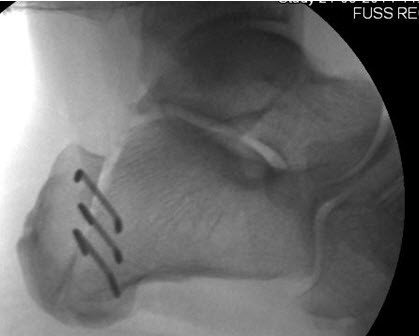

Nach diesem Eingriff ist eine Ruhigstellung des Fusses in einer Unterschenkelschiene mit Teilbelastung von 15 kg an Gehstöcken für sechs Wochen notwendig, damit der mit Klammern fixierte Knochen zusammenwachsen kann. (Abb. 2) Der Eingriff, der in Lokalanästhesie (Fussblock) durchgeführt werden kann, verlief komplikationslos; die Patientin konnte plangemäss nach zwei Nächten im Spital entlassen werden.

Nach gut zwei Wochen kam es unglücklicherweise zu einem Misstritt auf einer Treppe mit vollem Abstehen auf dem operierten Fuss. Aufgrund Schmerzen im Fersenbereich wurde eine Röntgenaufnahme durchgeführt, und eine leichte, aber noch akzeptable Verschiebung des hinteren Knochenfragments festgestellt. Die Klammern waren noch im Knochen verankert, so dass entschieden wurde, die Situation so zu belassen und nicht erneut zu operieren.

Die im Verlauf angefertigten Röntgenbilder dokumentierten eine gleichbleibende Stellung des Knochens mit langsamer Auffüllung des entstandenen Spalts mit sogenanntem Kallus (= neugebildeter Knochen). Aufgrund der verzögerten Knochenheilung als Folge der Verschiebung durfte die Patientin die Belastung erst mit vier Wochen Verspätung aufnehmen, wobei im Verlauf erneut Beschwerden auftraten. Ein weiteres Röntgenbild offenbarte, dass die Knochenheilung wider Erwarten nicht vorangeschritten und der Spalt bei unveränderten, im Prinzip guten Stellungsverhältnissen erneut deutlich sichtbar war.